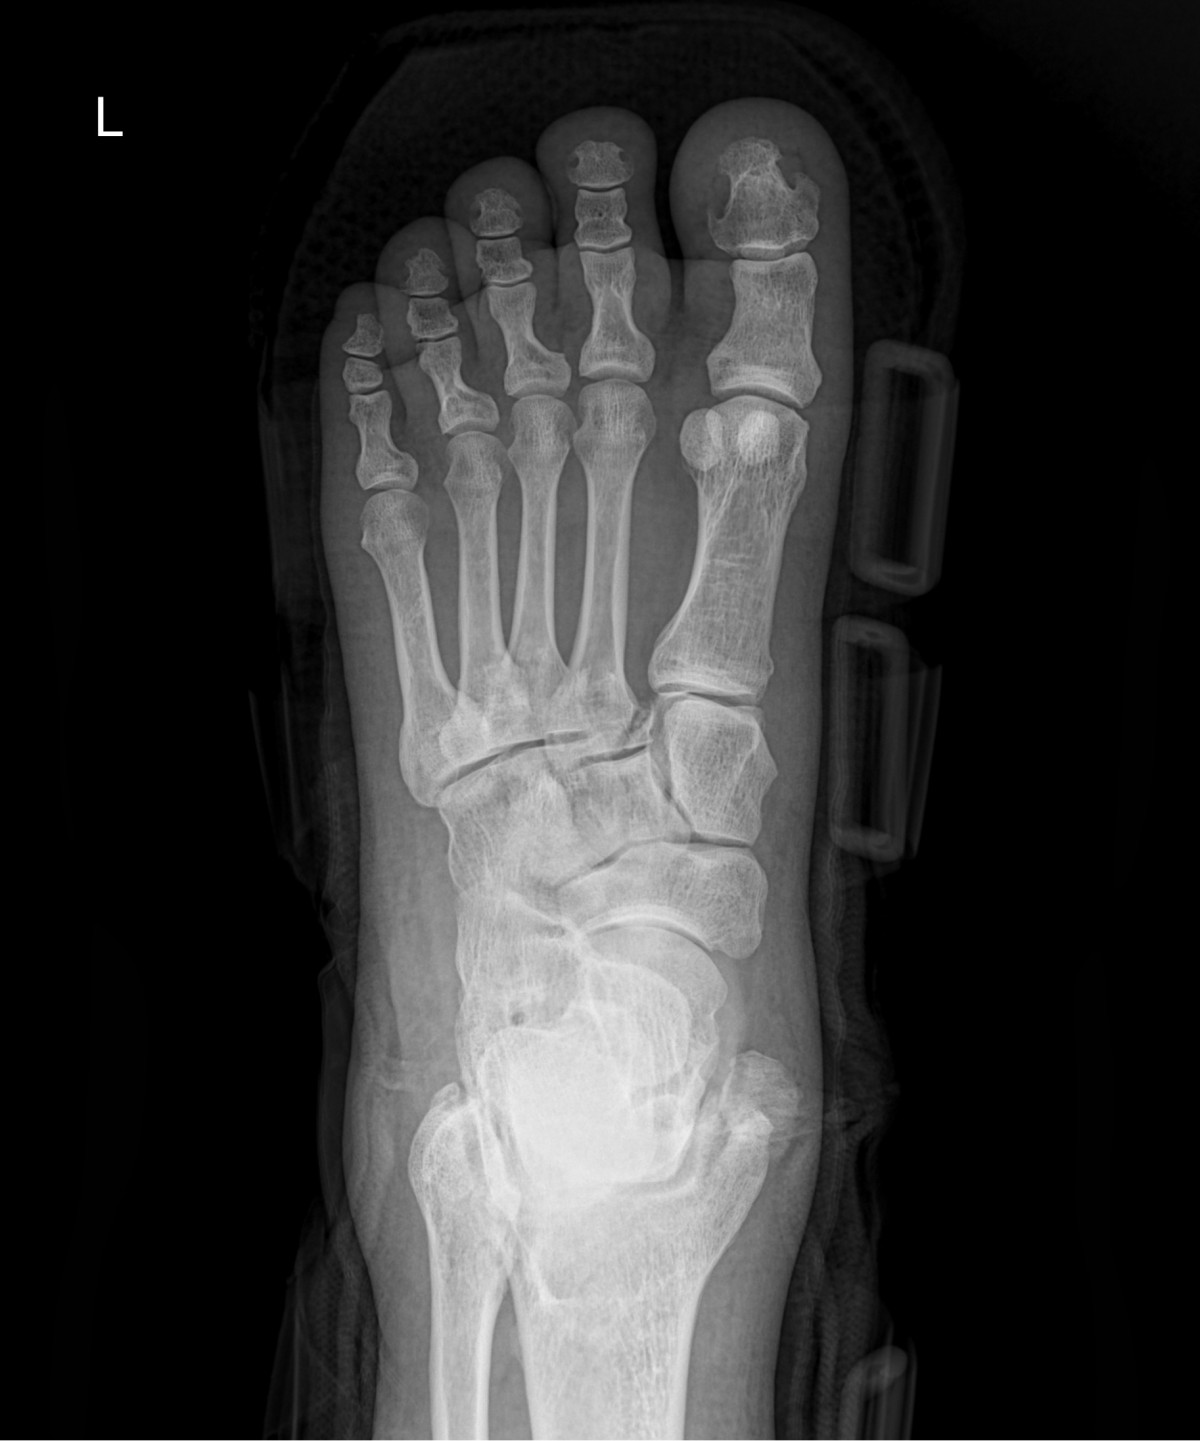

이재상원장님 발등 골절 수술 유현O 환자

dae765e4d9ac96aee867c9d6292d8784_1758003312_1522.jpg